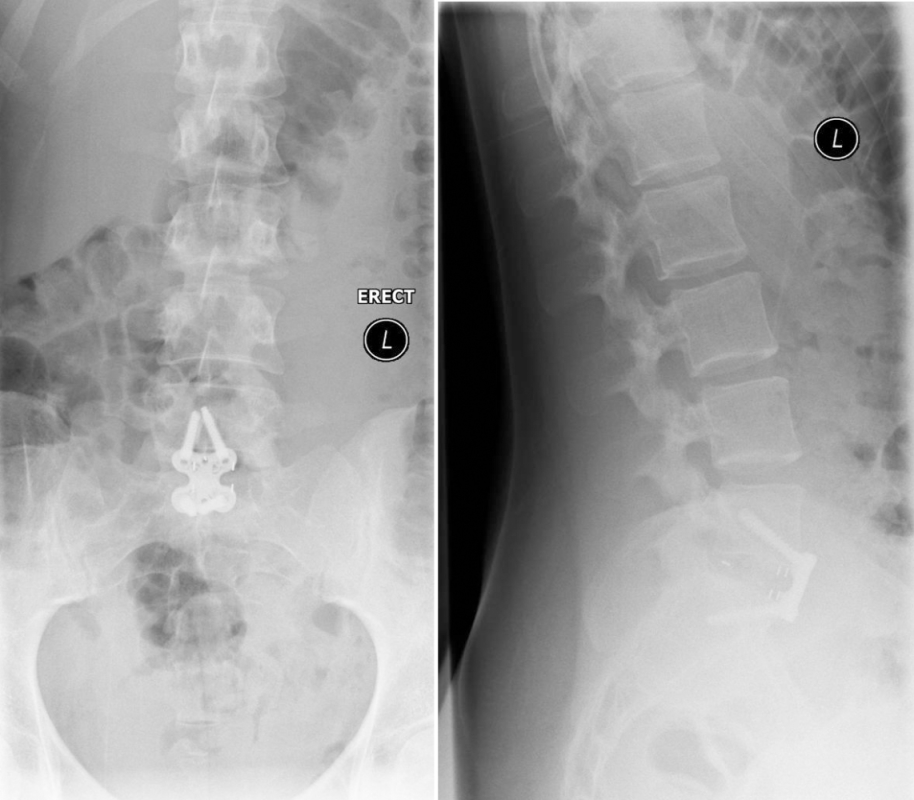

The postsurgery AP and lateral images show stand-alone locked L5/S1 anterior fusion using Syncage Evolution with BMP-2 and an Aegis locking plate (Fig 13).